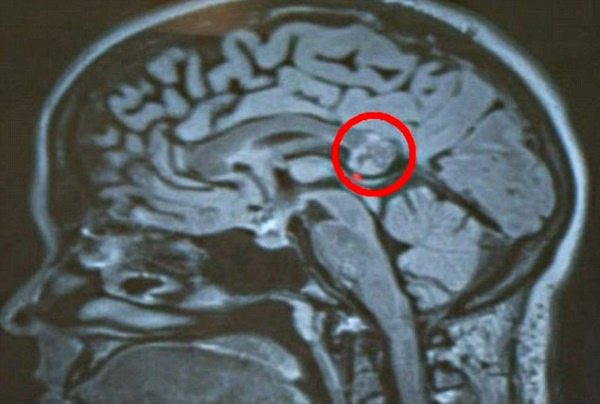

6 – Dentes no cérebro

Não é totalmente incomum para um bebê de quatro meses possuir dentes, a menos que eles estejam alojados no cérebro. E esse foi exatamente o caso de um bebê de Maryland, EUA, de acordo com um relatório publicado em fevereiro de 2014 pelo New England Journal of Medicine.

Os médicos suspeitavam que algo poderia estar errado dentro do cérebro da criança quando sua cabeça começou a crescer mais do que o habitual para a idade. Então, após exames no cérebro, notaram uma espécie de tumor que parecia ter dentes normalmente encontrados na mandíbula superior. E, de fato, após uma cirurgia de remoção, eles verificaram que realmente eram dentes.

Enquanto não é de todo incomum que dentes apareçam em tumores, o tipo encontrado no bebê, um craniofaringioma, não era conhecido por hospedar tais adições estranhas.